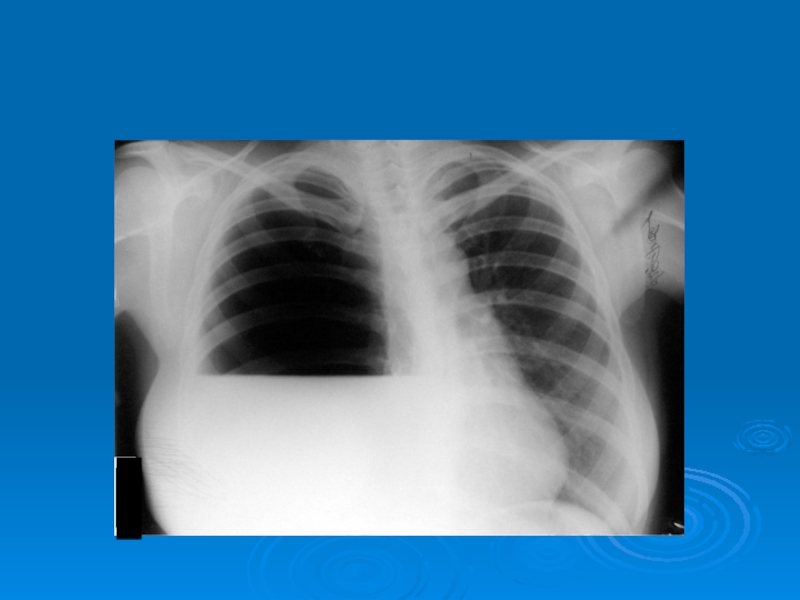

Слайд 44Рентгенограммы больных с абсцессами в правом и левом легком

Рентгенограммы больных с абсцессами в правом и левом легком